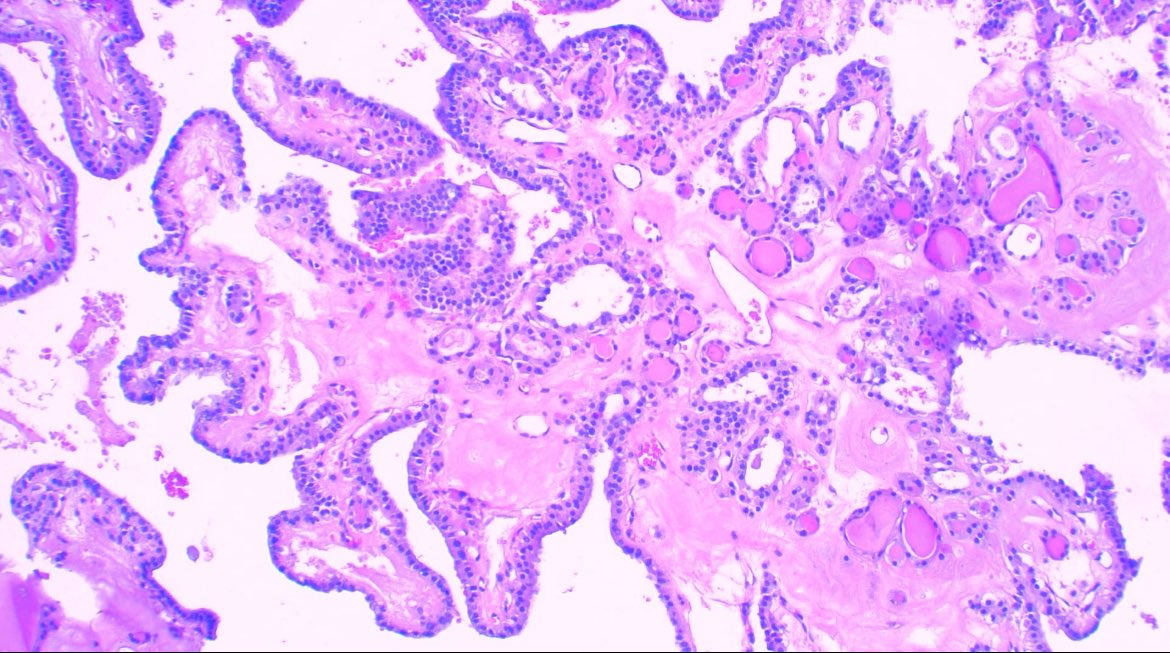

Papilla does not mean carcinoma in #thyroid #pathology Nodules with cystic degeneration can show beautiful ones 😁 Nuclear features are mandatory. #medicine #path #endocrine

JCandidoXavier's tweet image. Papilla does not mean carcinoma in #thyroid #pathology

Nodules with cystic degeneration can show beautiful ones 😁

Nuclear features are mandatory.